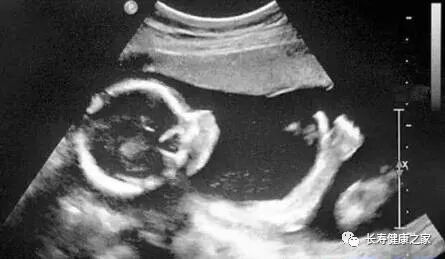

B超

像挑西瓜前敲一敲

B超的原理是用超声波穿透人体,当声波遇到人体组织时会产生反射波,通过计算反射波成像。就像挑西瓜一样,边敲边看显示病灶情况。

腹部盆腔

除肠道外,一般超声都能查

腹腔器官受呼吸影响较大,进而影响到CT、核磁成像,而超声不会因此受影响。同时,超声对肝脏、脾脏、胰腺、肾脏、盆腔脏器等诊断准确率较高。

但是超声受气体干扰很大,对于肠道等含气较多的器官,超声诊断准确率会降低。